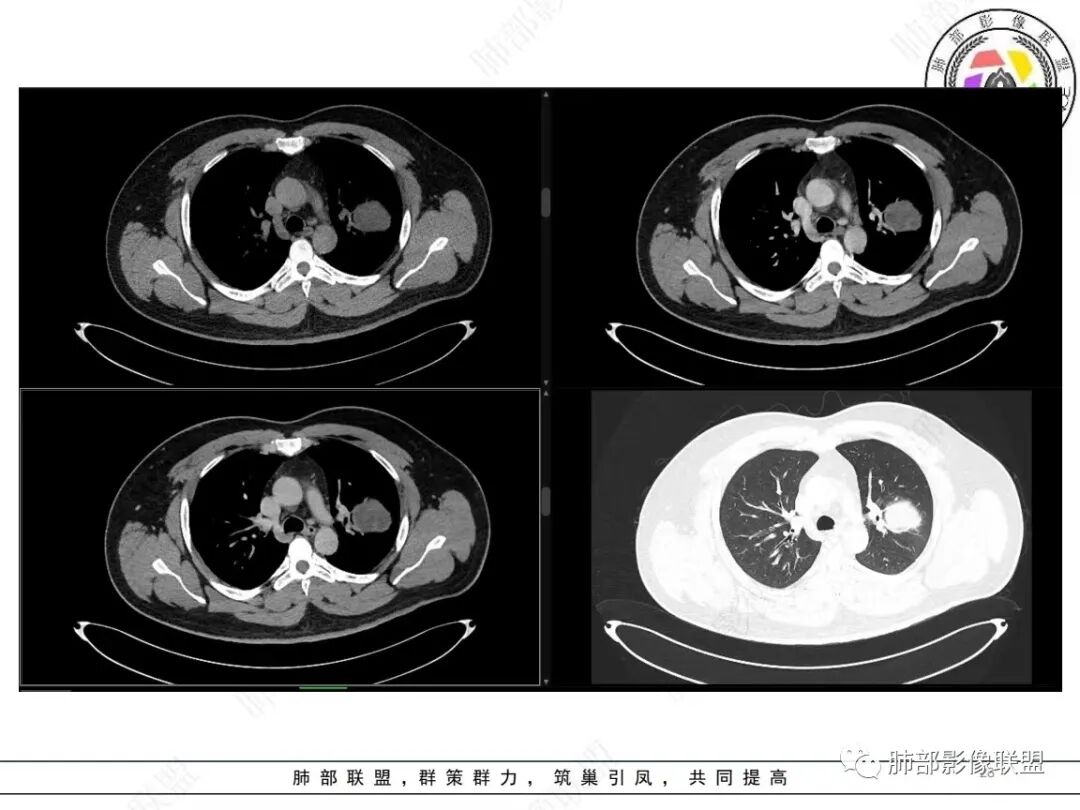

中年人,咳血,左肺上叶实性团块,边界清晰,与胸膜分界不清,可见栽赃表现,病灶推挤支气管及肺血管内移,增强可能条纹血管影,总体强化明显,考虑恶性或交界性肿瘤,间叶组织来源,肉瘤,SFT,肉瘤样癌,滑膜肉瘤。

左肺上叶胸膜肿块,浅分叶,边缘光整,密度不均匀,周围气管及血管受压推移,边缘强化,考虑肉瘤,鉴别SFT

左上肺软组织肿块,周围散在磨玻璃影,界不清,窄基底贴于胸壁,胸膜下脂肪间隙不清,呈低强化,胸膜下见。与主病灶强化方式一样的病变,2R区见肿大淋巴。考虑恶性,间叶组织来源合并出血。

青年男性,咯血;CT示左肺上叶胸膜下软组织肿块,边界尚清,宽基底与胸膜相连,增强动脉期内见细条状血管影,轻度延迟强化,定位:肺外,胸膜外脂肪存在,考虑脏层胸膜起源;定性:考虑SFT。

影像表现:左肺上叶占位合并出血,胸膜栽赃,边缘强化,局部见血管影,中心密度20Hu,无强化,符合非液化坏死。定位:肺内,定性恶性(明显血管影,栽赃排除错构瘤,中心无强化排除PSP,无明显清楚的坏死边界,强化不符合肉芽肿,排除结核),年龄轻,无长时间吸烟史和肺气肿改变,肉瘤样癌可能性很小,与支气管无确切关系,所以病理类型考虑来源于肺间叶组织的肉瘤,骨外尤文?滑膜肉瘤?

有血供,强化不明显,周围肺出血,肺组织受压改变,定位肺外,胸膜增厚,部分胸膜下脂肪间隙存在,不确定肋骨是否受侵犯,部分层面与肺动脉分界不清,感觉推移,如果供血要考虑sft,强化不符合,有血管进入,但是强化不明显,密度相对均匀,所以不考虑坏死,富含粘液可能,咯血,说明累及支气管了,有一定侵袭性,肿块大,考虑间叶来源肿瘤,与胸膜接触面相对不是宽基底,综合考虑滑膜肉瘤可能,典型的滑膜肉瘤一般铺路石改变,这个又觉得信号相对均匀了一些学习中

定位肺内明确,来源间叶组织明确,年龄和吸烟史情况排除肉瘤样癌,剩下的就基本上只有骨外尤文和滑膜肉瘤了,再加上强化低,骨外尤文就肯定首先考虑。